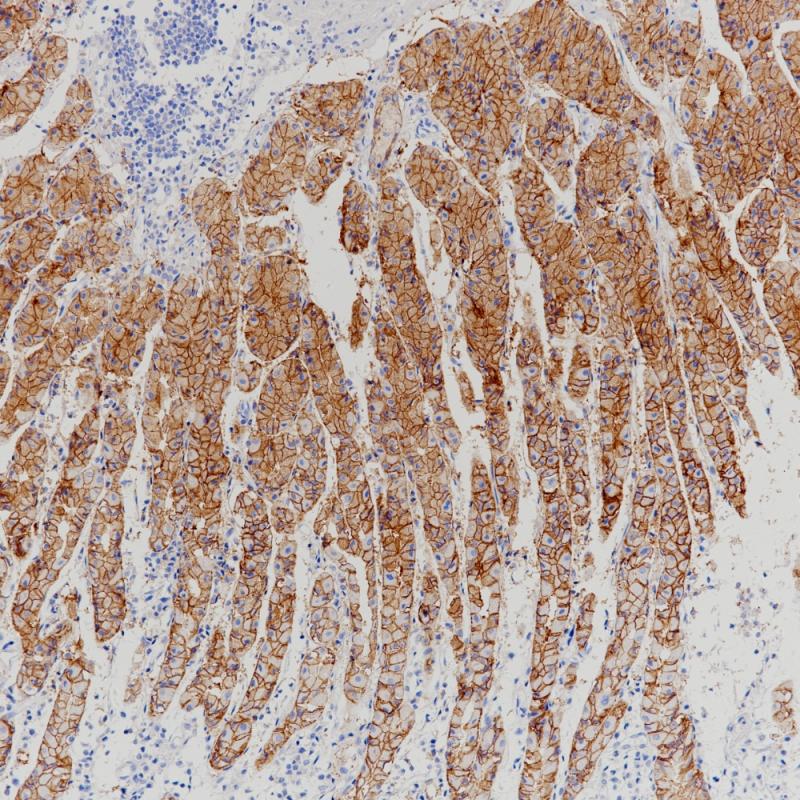

胃癌Claudin 18.2(BP6249)染色

胃Claudin 18.2(BP6249)染色

肺腺癌Claudin 18.2(BP6249)染色